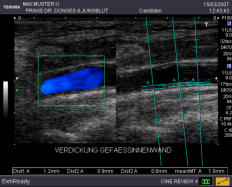

EKG Im Ruhe-EKG sehen wir Herzrhythmusstörungen, abgelaufene Infarkte oder Entzündungen des Herzmuskels. Belastungs-EKG Hier bekommen wir Hinweise auf Ihre körperliche Leistungsfähigkeit und können die Durchblutung der Herzkranzgefäße besser als im Ruhe-EKG beurteilen. Bei verengten Kranzgefäßen zeigt sich oft eine spezielle EKG-Veränderung während der Belastung, ein Herzdruck und/oder Luftnot. Herzultraschall Hier können wir genau die Pumpkraft Ihres Herzens und die Funktion der Herzklappen untersuchen, wir erkennen Infarktnarben, Klappenkrankheiten, Gerinnsel und Gewächse. Der Blutfluss durch die Herzkammern und Klappen kann mit speziellen Verfahren sicht- und hörbar gemacht werden (Farbdoppler). In die Kranzgefäße selbst können wir nicht sehen, aber aus der Beurteilung der Pumpfunktion wichtige Hinweise auf die Durchblutung erhalten. Eine exakte Aussage zu Verengungen der Herzkranzgefäße kann bei entsprechenden Hinweisen aus den Untersuchungen mit einem Herzkatheter getroffen werden. Halsschlagader-Messung Mit unseren hochempfindlichen Geräten können wir den Innendurchmesser der Halsschlagader (Carotis) genau ausmessen. Als Frühzeichen einer beginnenden Aderverkalkung nimmt diese sogenannte Intima-Media Dicke über das Altersmaß hinaus zu. Hieraus ergeben sich wichtige Konsequenzen, so z. B. die Beantwortung der Frage, ob ein erhöhter Cholesterinspiegel schon medikamentös behandelt werden muss.